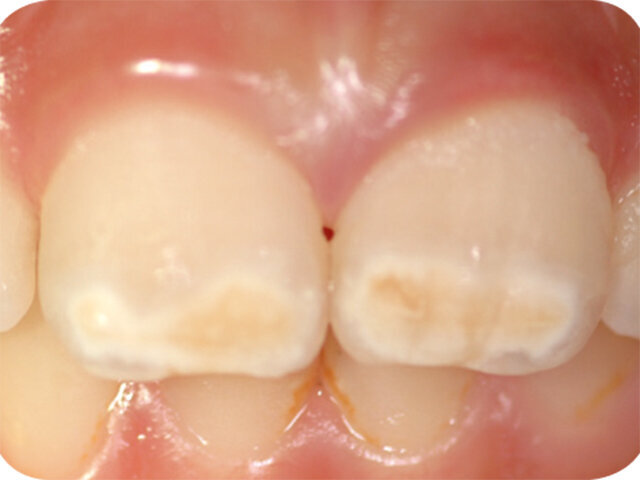

Molárová a incizální hypomineralizace skloviny (Molar Incisor Hypomineralisation – MIH) je globální problém postihující každé sedmé dítě. MIH je běžná vývojová porucha postihující především jeden nebo více prvních stálých molárů. Centrální řezáky mohou být rovněž postiženy, většinou však v menší míře. Může též dojít k hypomineralizaci druhých dočasných molárů (Hypomineralised Lesions on Second Primary Molars – HSPM, hypomineralizační léze druhých stálých molárů) nebo špičáků. U dětí s HSPM je až pětkrát vyšší pravděpodobnost vzniku MIH u stálého chrupu. Závažnost se velmi liší od mírných opacit k posterupčnímu odlomení skloviny.

Klinický vzhled

- Ohraničené opacity v rozpětí od krémově bílé, přes žlutou až po hnědé diskolorace

- Léze na centrálních řezácích jsou obvykle mírnější, někdy však mohou být neestetické